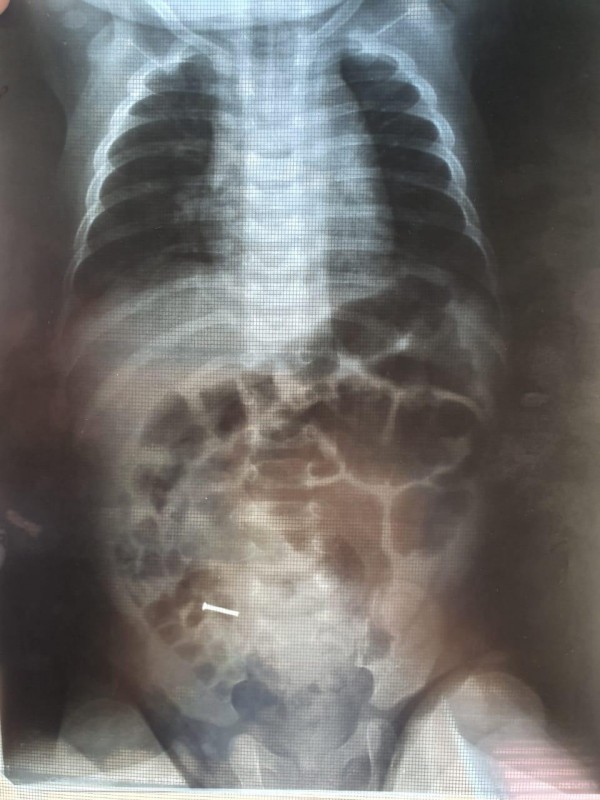

"Родители ребенка изначально обратились к врачам шымкентской городской клинической больницы по поводу того, что у малыша болели суставы. Специалисты-ортопеды при рентгене случайно обнаружили в желудочно-кишечном тракте ребенка железо, и ему была оперативно проведена операция, ведь над малышом нависла реальная угроза: гвоздь мог проколоть внутренние органы. Операцию провели квалифицированные врачи из городской детской больницы: Султангали Сарыбай, Амантаев Жаксылык, Курманалиев Асанбай. Во время операции хирурги смогли точно обнаружить инородное тело и извлечь его из желудка", - говорится в официальном сообщении.